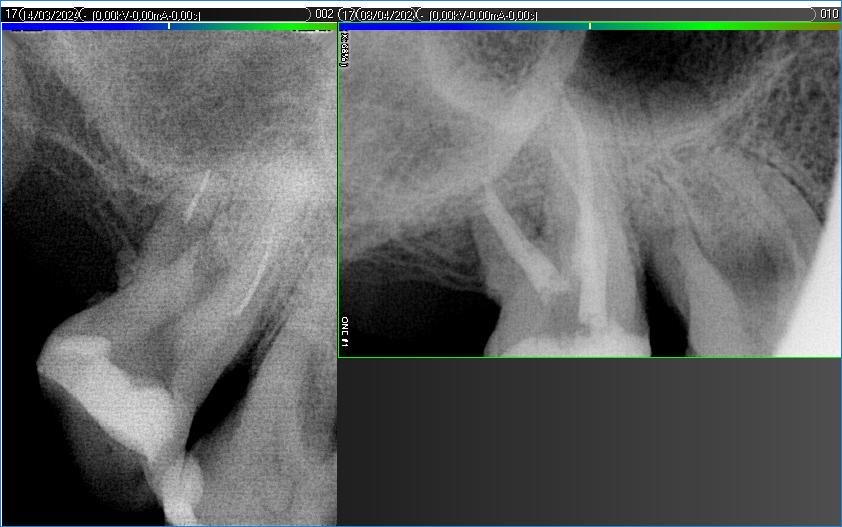

Вилучення інструменту з каналів зуба